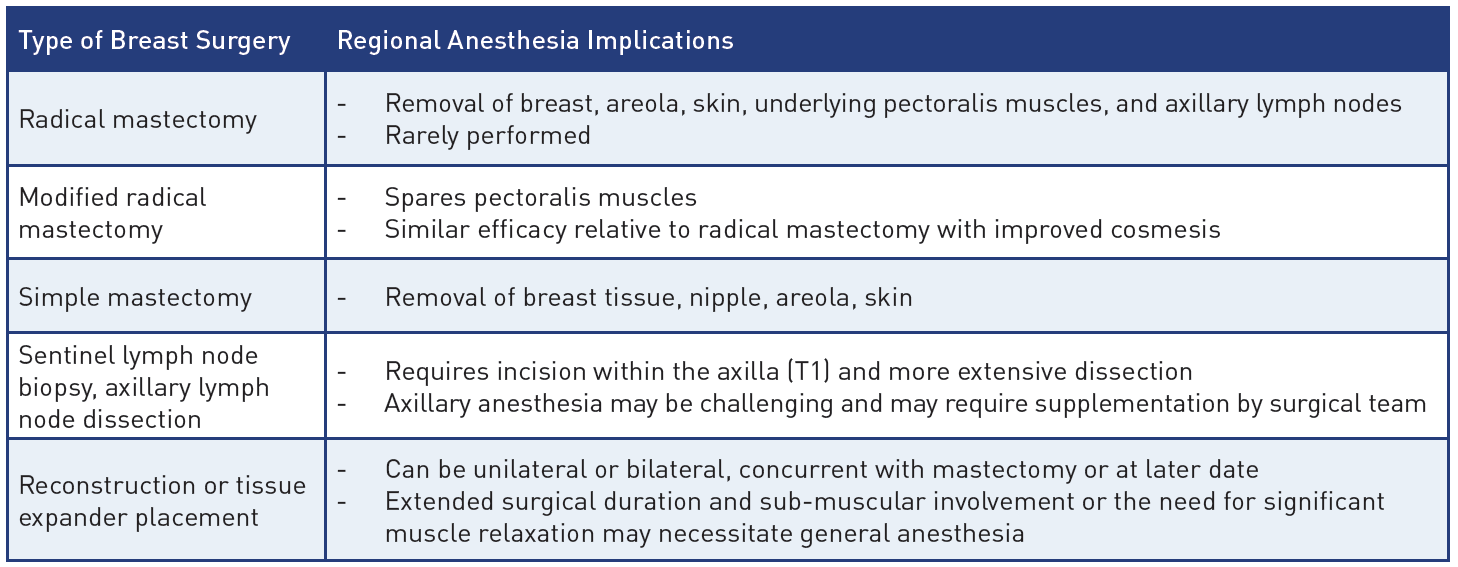

Table 1: Breast surgeries and their regional anesthesia implications

Table 2: Differences between regional anesthesia techniques for breast surgery